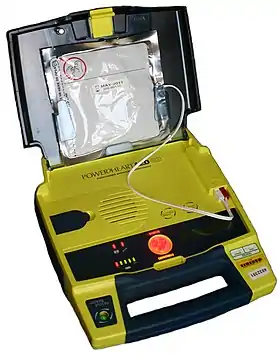

Defibrillators produce a defibrillation (electric shocks) that can restore the normal heart function of the victim.

Nevertheless, they are only indicated for some arrhythmias (abnormal heart beatings), specifically ventricular fibrillation (VF) and pulseless ventricular tachycardia. Defibrillation is not indicated if the patient is conscious or has a normal pulse. Defibrillation is also not indicated if the heart has completely stopped, as in asystole or pulseless electrical activity (PEA), in those cases a normal CPR would be used to oxygenate the brain until the heart function can be restored. Improperly given electrical shocks can cause dangerous arrhythmias, such as the ventricular fibrillation (VF).[45]

The standard defibrillation device, prepared for a fast use out of the medical centres, is the automated external defibrillator (AED), a portable machine of small size (similar to a briefcase) that can be used by any user with no previous training. That machine produces recorded voice instructions that guide to the user along the defibrillation process. It also checks the victim's condition to apply automatically electric shocks at a correct level, if they are needed. Other models are semi-automatic and need that the user push a button before producing an electric shock.

The defibrillation process is simple, but there exist written instructions of defibrillators that explain it step-by-step.

There are several devices for improving CPR but, only defibrillators (as of 2010) have been found better than standard CPR for an out-of-hospital cardiac arrest.[5]